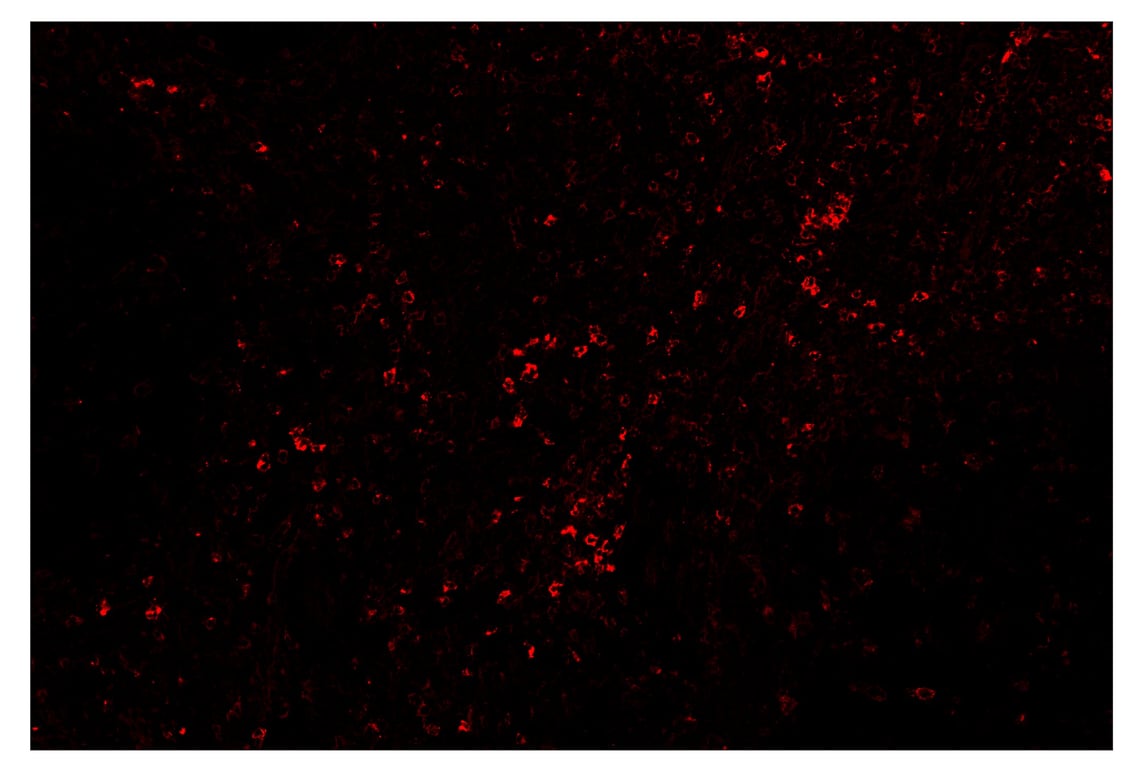

SignalStar™ immunohistochemical analysis of paraffin-embedded human tonsil using TIM-3 (D5D5R™) & CO-0010-647 SignalStar™ Oligo-Antibody Pair #15231 (red). All fluorophores have been assigned a pseudocolor, as indicated. Staining was performed on the BOND RX by Leica Biosystems.

Immunohistochemistry Image 4: TIM-3 (D5D5R<sup>™</sup>) & CO-00010-488 SignalStar<sup>™</sup> Oligo-Antibody Pair